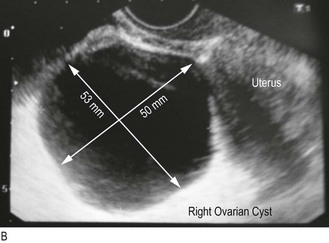

Pain in either iliac fossa may be due to ovarian cysts, cyst conditions, e.g. haemorrhage, rupture or torsion, or diseased Fallopian tubes. Infection, pelvic adhesions and endometriosis can cause generalised pain (Boxes 10.9 and 10.10).

These can cause abdominal distension and pressure effects or be asymptomatic. The most common is a pregnant uterus. Uterine leiomyoma (fibroids) or ovarian cysts are other causes.